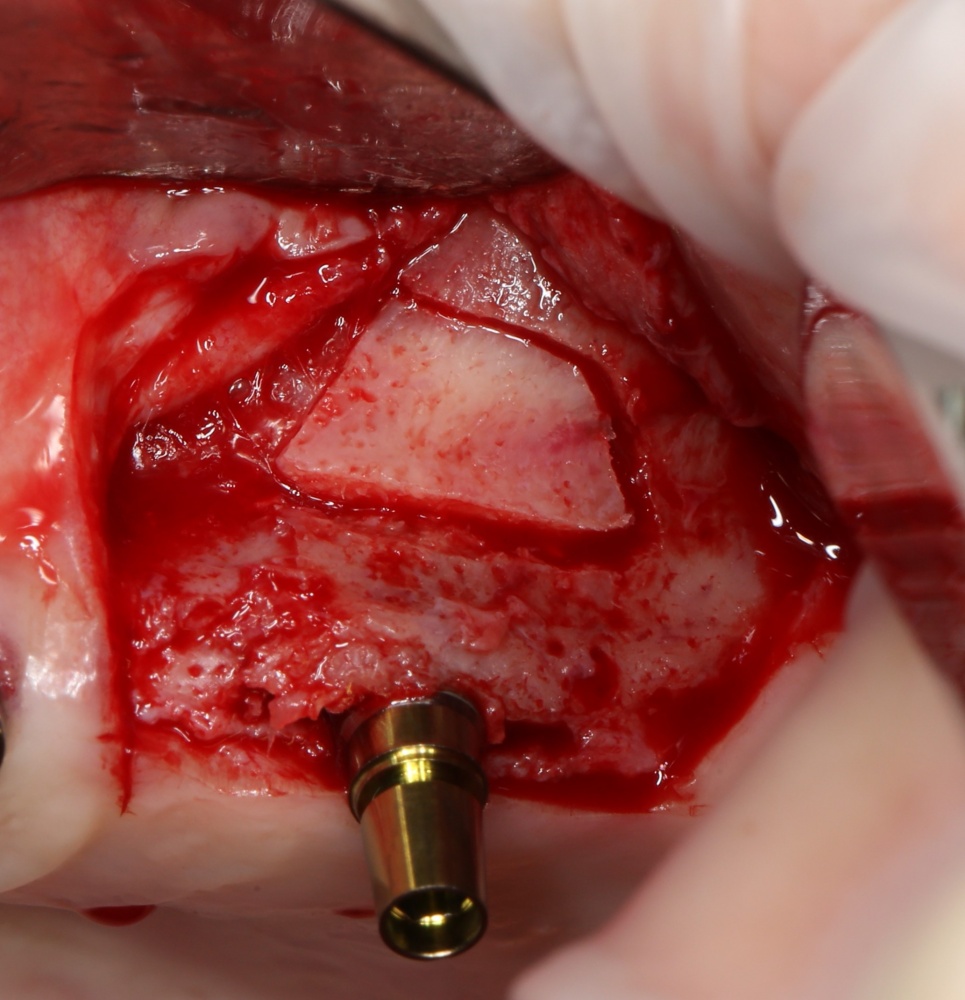

Простой синуслифтинг. Часть I.